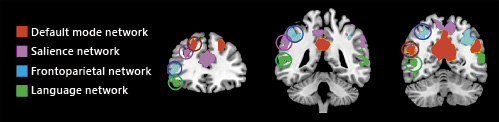

The reason for these internetwork changes following tDCS remains to be elucidated. Between-networks effects may be related to accidental (co)stimulation of directly adjacent brain regions, which in turn may cause multiple network effects and even unexpected negative effects on cognitive outcomes [59]. To resolve this issue, rs-fMRI could be used to identify non-overlapping hubs from specific networks. Indeed, procedures of signal decomposition such as independent component analysis (ICA) enable to extract distinct (spatially non-overlapping) nodes for each network (Fig. 3). However, some degree of overlap between networks might be unavoidable. Macroscopic anatomical brain connectivity studies suggest a so-called “rich club” organization of the brain, whereby highly interconnected nodes show a strong tendency to connect with other highly connected nodes, thus resulting in numerous between-network connections [65]. While the sensorimotor network shows a relatively small proportion of rich club nodes (6–8%), the DMN, SN, and FPN show considerably more rich club nodes (up to 23%) [66]. Thus, although different DLPFC and posterior parietal subregions are exclusively part of a network, they may be highly interconnected, and this observation may, in part, explain the different neuromodulatory effects reported in the studies above. Conversely, the lower proportion of rich club within the sensorimotor network may explain the higher consistency between studies targeting motor cortex with atDCS electrodes and the relatively selective effect on this network.

Non-overlapping hubs for the major cognitive networks (language, frontoparietal, salience, and default mode networks). Maps were extracted through independent component analysis from a sample of 20 healthy subjects and overlaid into the MNI template. Circles highlight the spatial localization of non-convergent dorsal frontal and parietal hubs of each functional network.

Non-overlapping hubs for the major cognitive networks (language, frontoparietal, salience, and default mode networks). Maps were extracted through independent component analysis from a sample of 20 healthy subjects and overlaid into the MNI template. Circles highlight the spatial localization of non-convergent dorsal frontal and parietal hubs of each functional network.